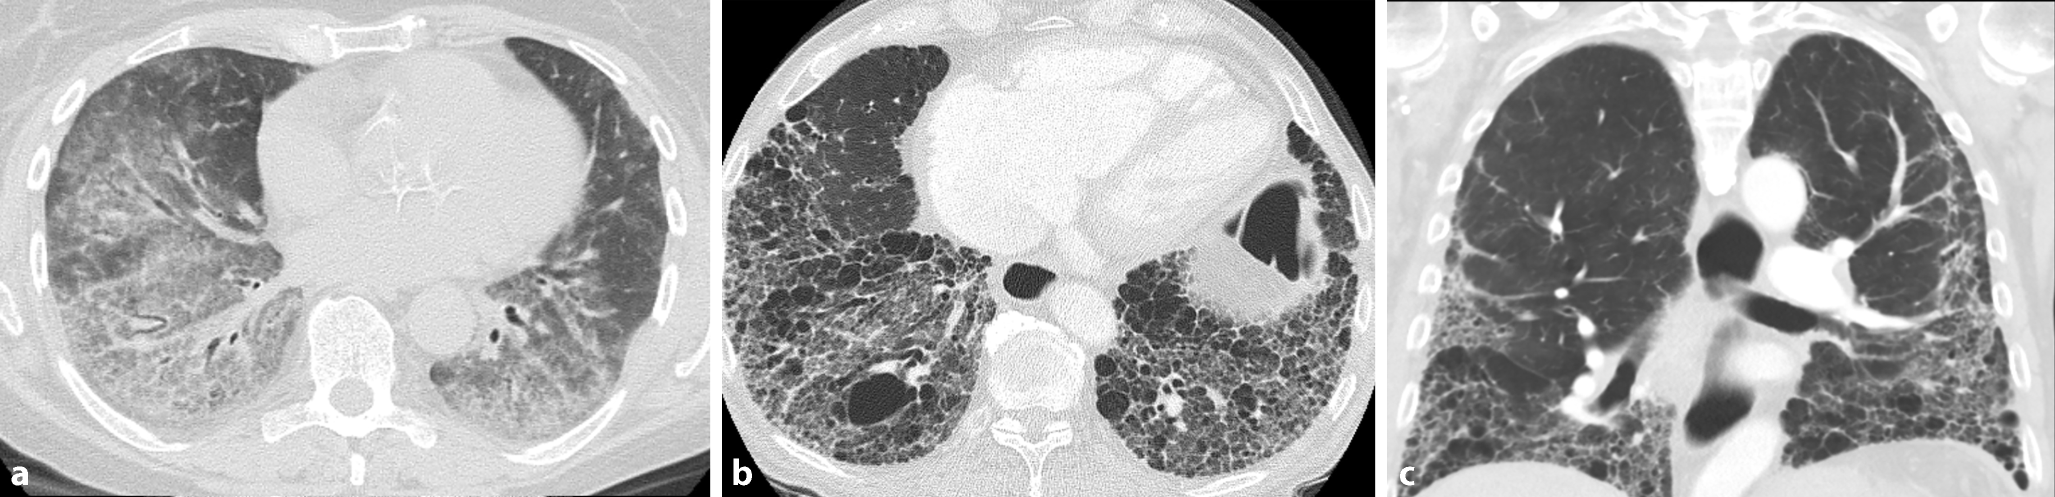

Das häufigste auftretende radiologische Muster bei einer SSc-ILD ist die nichtspezifische interstitielle Pneumonie (NSIP: überwiegend Milchglasinfiltrate, kein „honeycombing“, keine ausgeprägten Traktionsbronchiektasen) mit 70–80 %, gefolgt von der gewöhnlichen interstitiellen Pneumonie (UIP: wenige oder keine Milchglasinfiltrate aber „honeycombing“ oder ausgeprägte Traktionsbronchiektasen) in 10 % der Fälle (Abb. 3; [29]).

Abb. 3

SSc-typische Veränderungen in der HRCT. a NSIP-Muster mit überwiegend Milchglasinfiltraten. b UIP-Muster ohne Milchglasinfiltrate, aber mit ausgeprägtem „honeycombing“ und Traktionsbronchiektasen. c Ebenfalls UIP-Muster, aber hier gut dargestellt die basale Betonung der Lungenveränderungen bei der SSc-ILD

Bild vergrößern

HRCT-Muster bei SSc-ILD:

• Milchglasinfiltrate: Diese stellen unscharf begrenzte, erhöhte Dichteareale dar, die auf eine aktive Entzündung oder beginnende Fibrose hinweisen. Milchglasinfiltrate sind oft ein frühes Zeichen einer SSc-ILD und deuten auf reversible Krankheitsprozesse hin. Ihre Anwesenheit kann auf eine potenzielle Ansprechbarkeit auf eine immunsuppressive Therapie hindeuten.

• Retikuläres Muster: Diese Strukturveränderungen resultieren aus der Verdickung der interlobulären Septen und subpleuralen Lungenareale. Sie signalisieren eine fortschreitende Fibrosierung und sind häufig in Verbindung mit Milchglasinfiltraten zu finden. Das Vorhandensein von retikulären Veränderungen zeigt eine fortgeschrittenere Krankheitsphase an.

• Traktionsbronchiektasen: Diese entstehen durch den zunehmenden fibrotischen Zug an den Bronchien, was zu einer irreversiblen Erweiterung der Atemwege führt. Ihre Präsenz in der HRCT ist ein Hinweis auf eine bereits chronische und fortschreitende Erkrankung.

• „Honeycombing“: Diese schwerwiegenden Veränderungen sind gekennzeichnet durch kleine, regelmäßig angeordnete Zysten mit verdickten Wänden und stellen ein typisches Zeichen für eine fortgeschrittene Lungenfibrose dar. Entsprechende Strukturänderungen sind typischerweise in den subpleuralen Regionen der Lunge lokalisiert, weisen auf eine irreversible Zerstörung des Lungengewebes hin und sind oft mit einer besonders schlechten Prognose assoziiert.

Radiologische Zeichen einer pulmonalen Fibrose finden sich bei bis zu 90 % aller SSc-PatientInnen, Milchglasinfiltrate bei 50 % [29], „honeycombing“ bei bis zu einem Drittel der Patienten [30]. Das Ausmaß der Lungenveränderungen in der HRCT-Untersuchung korreliert invers mit der FVC und hängt stark mit der Mortalität zusammen [31]. Ein Lungenemphysem kann unabhängig von den bereits genannten Mustern vorhanden sein, wobei eine kombinierte pulmonale Fibrose mit auch Lungenemphysem in etwa 7–18 % der Patienten mit SSc-ILD auftritt und mit einer schlechteren Prognose assoziiert ist [3234].